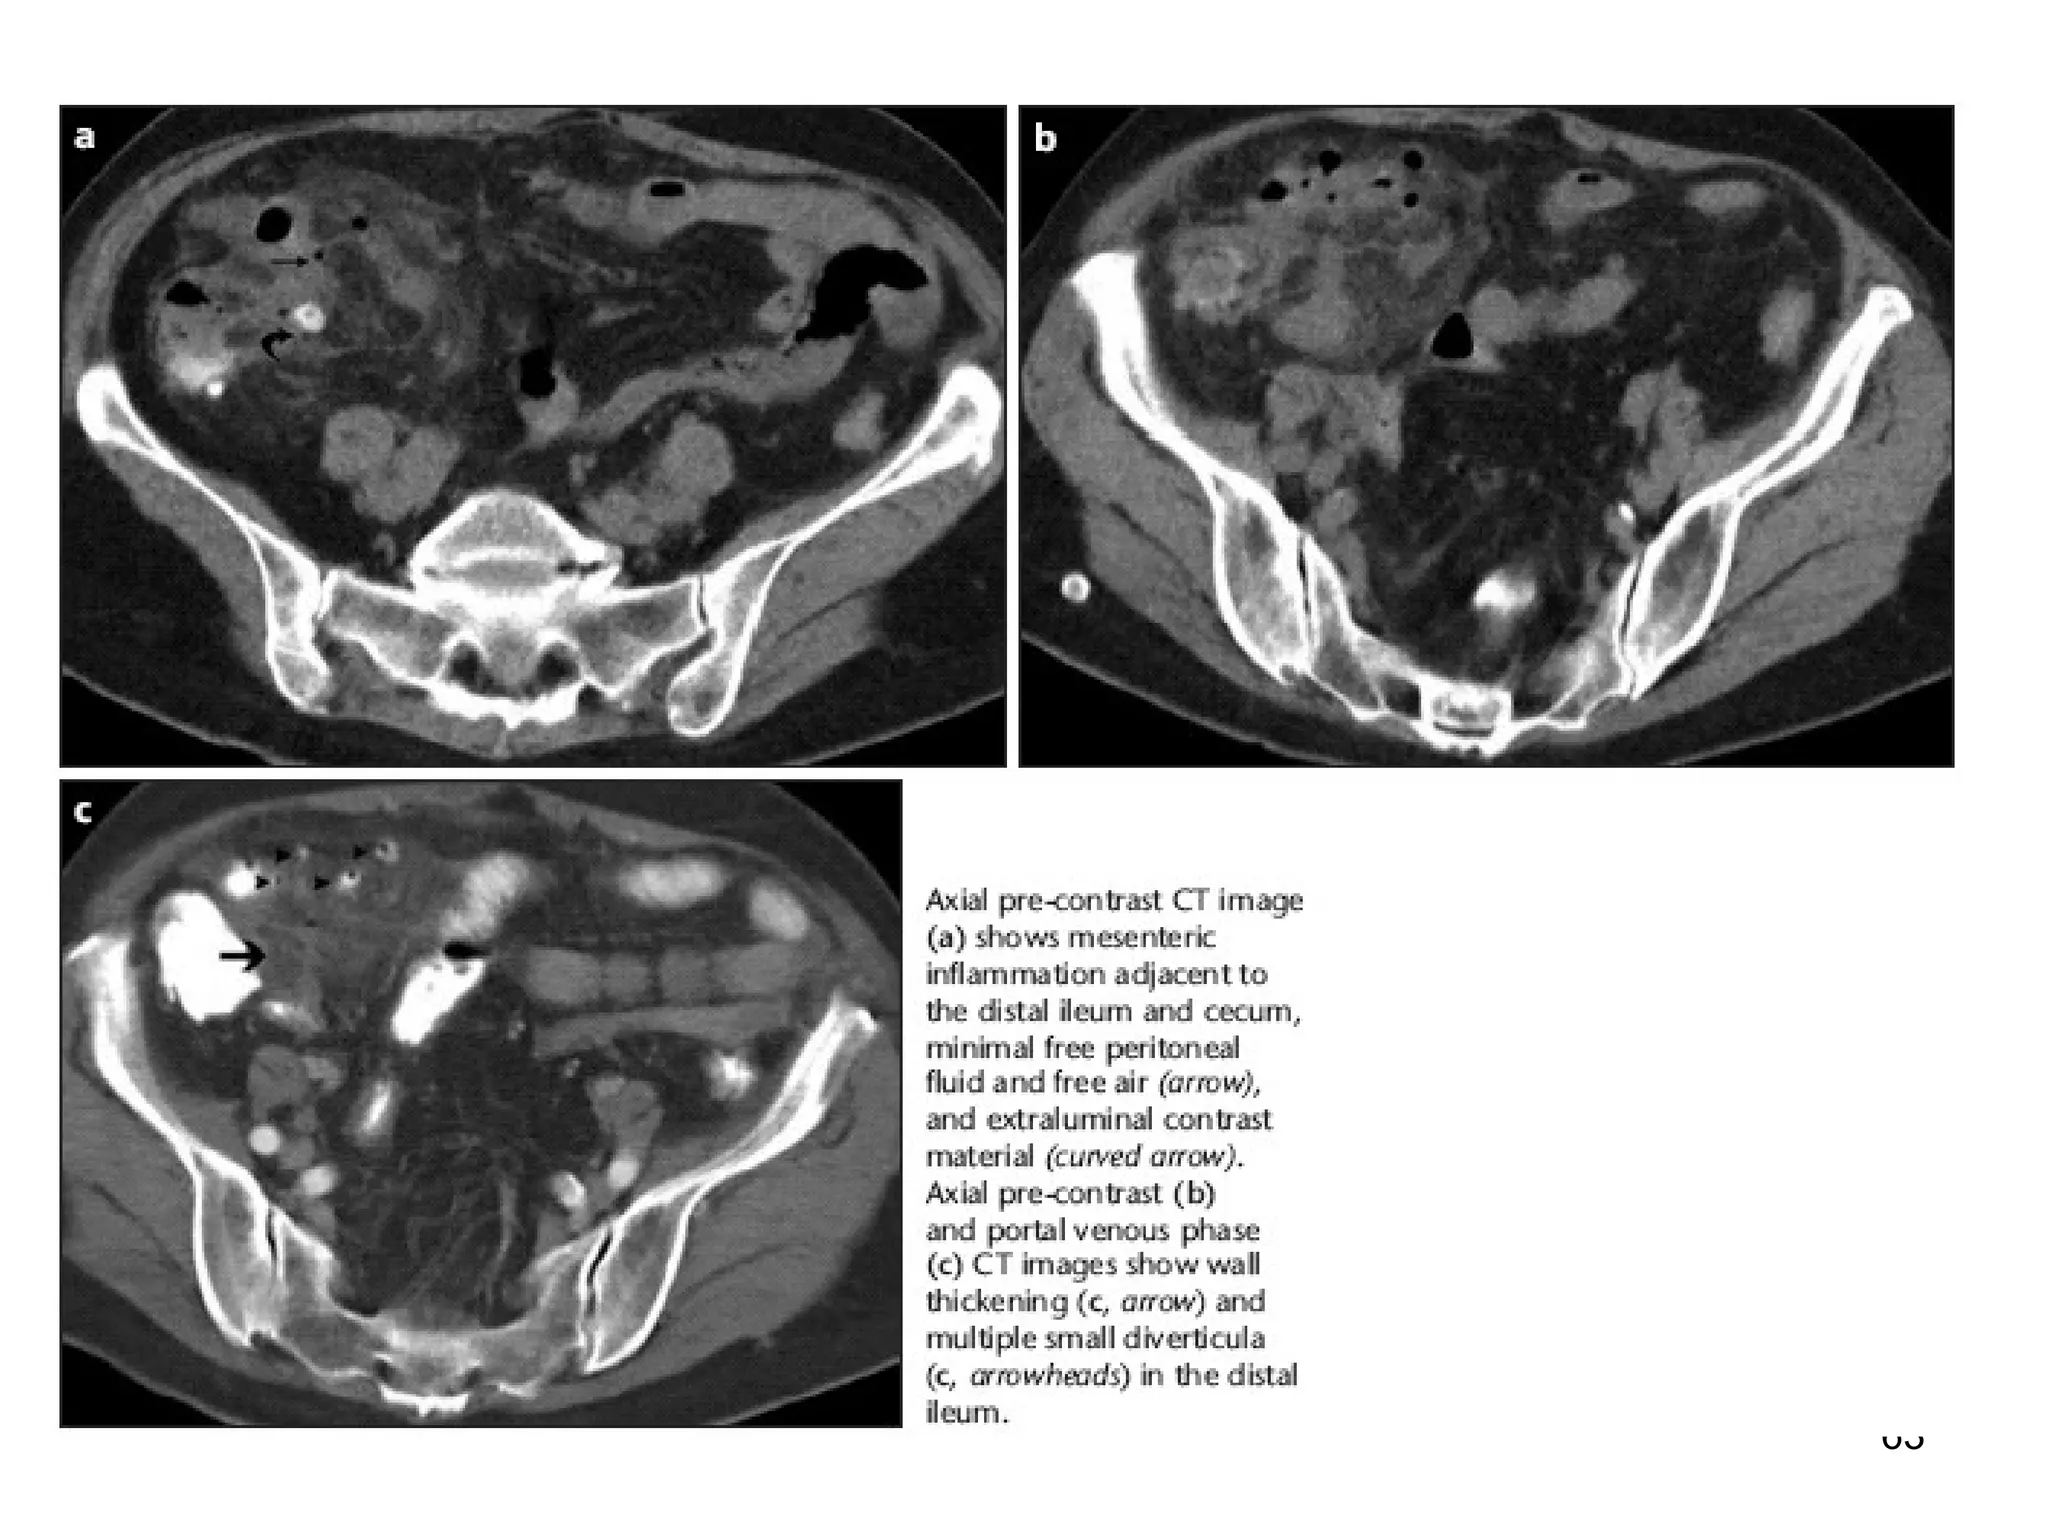

be seen at D-Jflexure and terminal ilenm

61 CT with freeair and bowel loop

Backwash ileitis" due to ulcerative colitis. Note features of chronic ulcerative

colitis in right colon, patulous ileocaecal valve, dilated distal ileum with

granular mucosa.

25 Backwash ileitis" dueto ulcerative colitis. Note features of chronic ulcerative colitis in right colon, patulous ileocaecal valve, dilated distal ileum with granular mucosa.